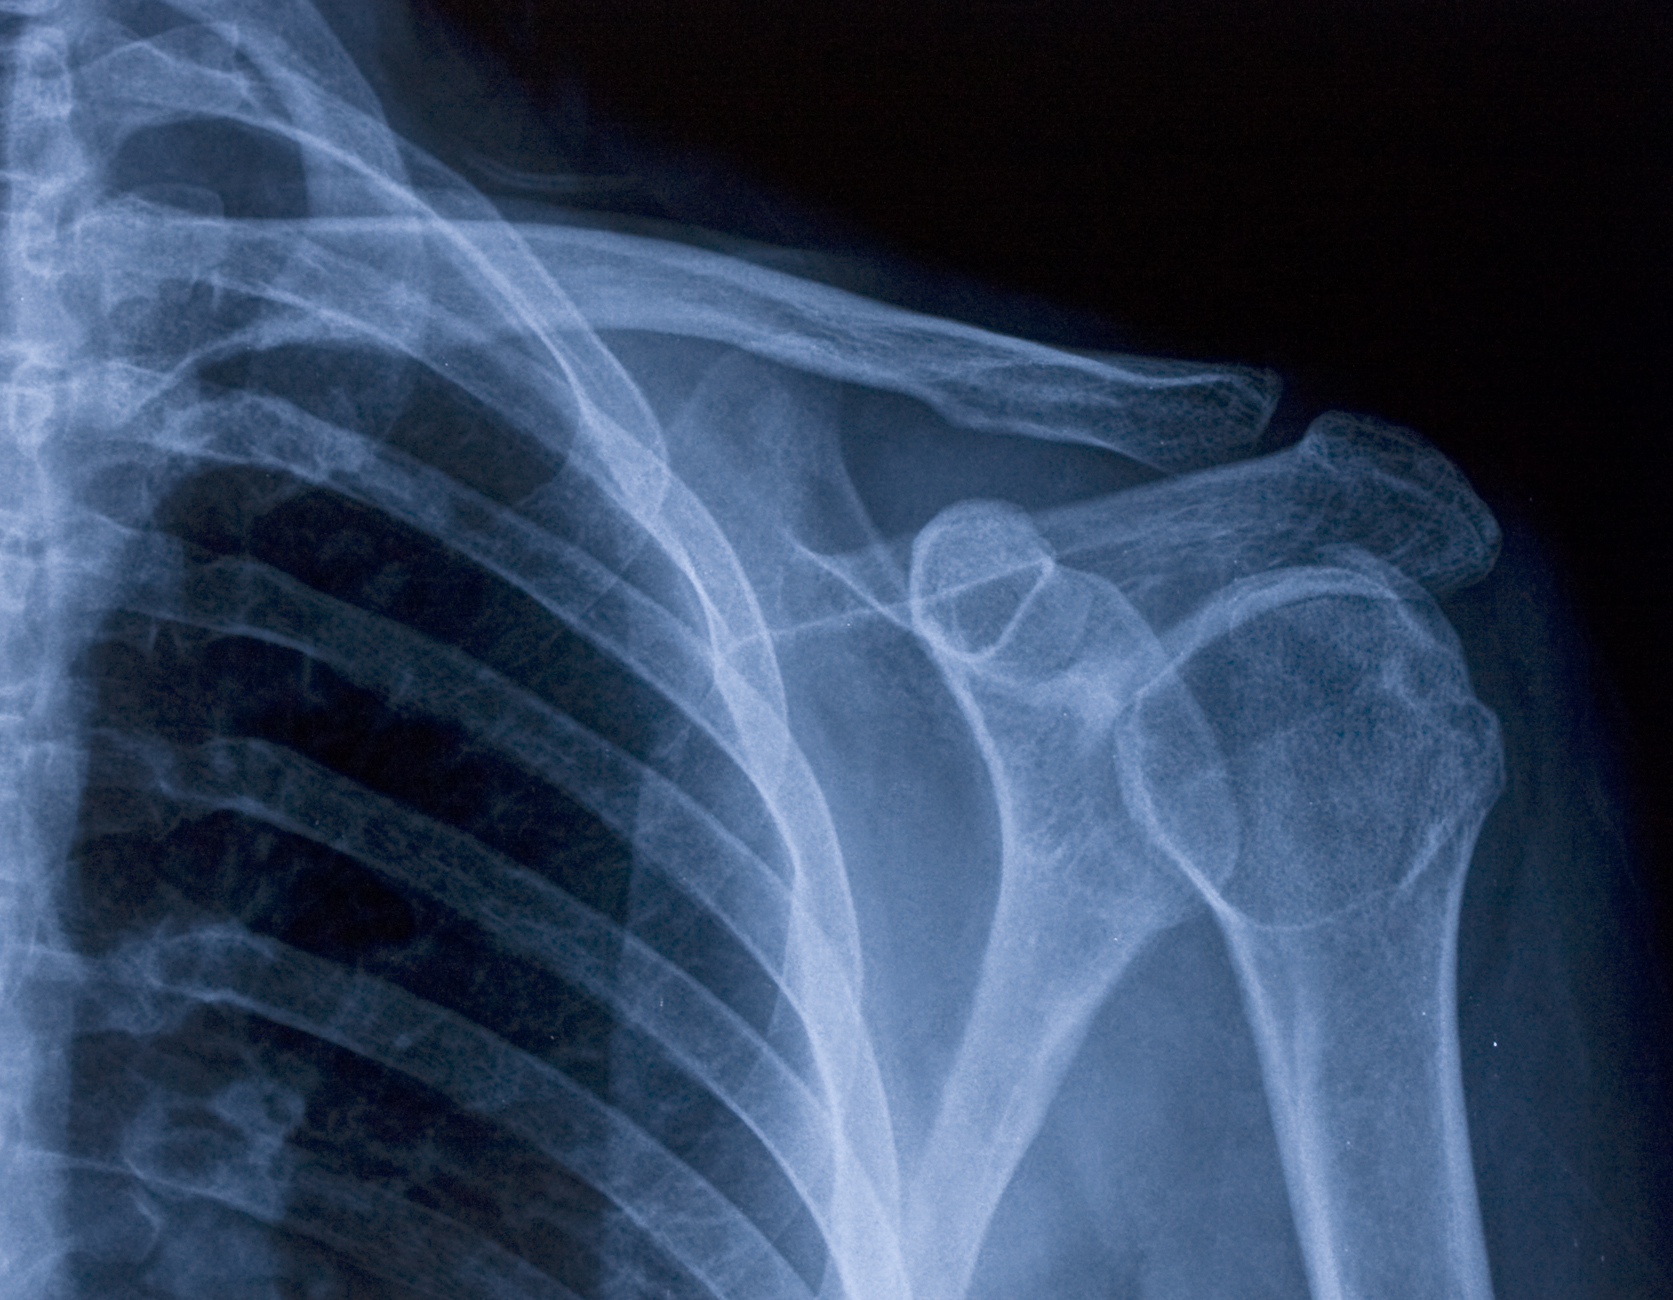

WorkCover imaging includes diagnostic scans like X-rays, CT scans, and ultrasounds used to assess injuries sustained at work. These tests help your doctor evaluate your condition accurately and support your workers’ compensation claim.

At Link Radiology, we use the latest low-dose digital imaging technology to provide clear, detailed scans. Our expertise in WorkCover imaging ensures accurate diagnosis and fast reporting to help manage your recovery efficiently.

Based in Albany Creek, Link Radiology offers a full range of WorkCover imaging including X-rays, CT scans, MRI, and ultrasound. We work closely with your doctor and insurer to provide timely, reliable results to support your treatment and claim.